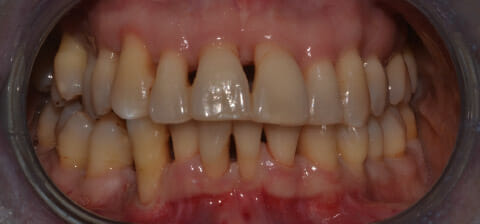

Endorale prima e dopo la cura della parodontite

Con terapia parodontale fotodinamica non chirurgica: si noti la ricrescita naturale dell’osso e del tessuto parodontale.